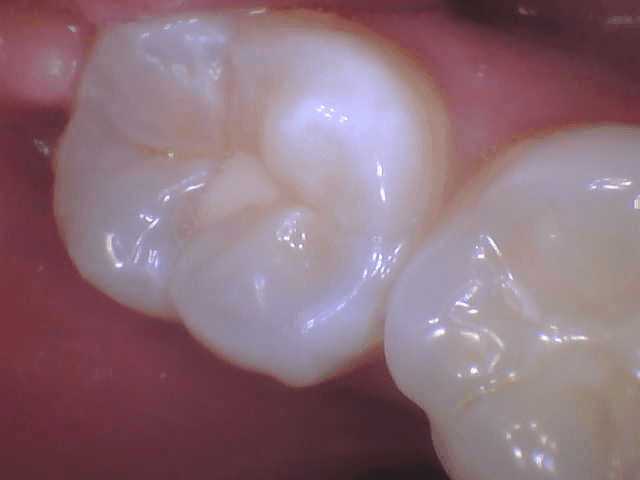

Intraoral Cameras

When you understand your treatment and are given choices in your care, it takes a lot of the anxiety out of dentistry. Intraoral cameras go a long way toward accomplishing these objectives.

The cameras are small, about the size of an ink pen. However, they capture close images of your teeth and gums. Your Lower Templestowe dentist can then project these images onto a chairside monitor and explain how various treatments can help a specific problem or how a recommended therapy may combat an oral health issue. This technology informs and educates, assisting you to make informed oral health decisions going forward.